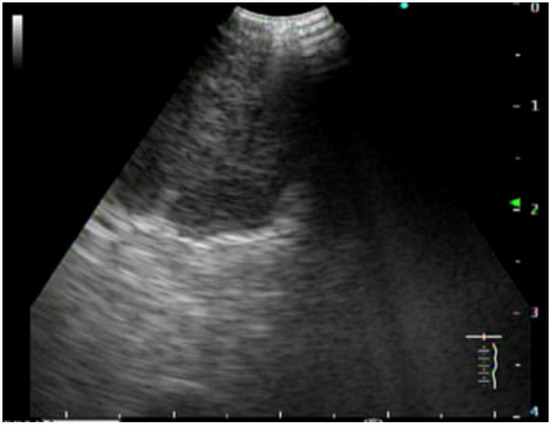

5.1. Endoscopic Staging